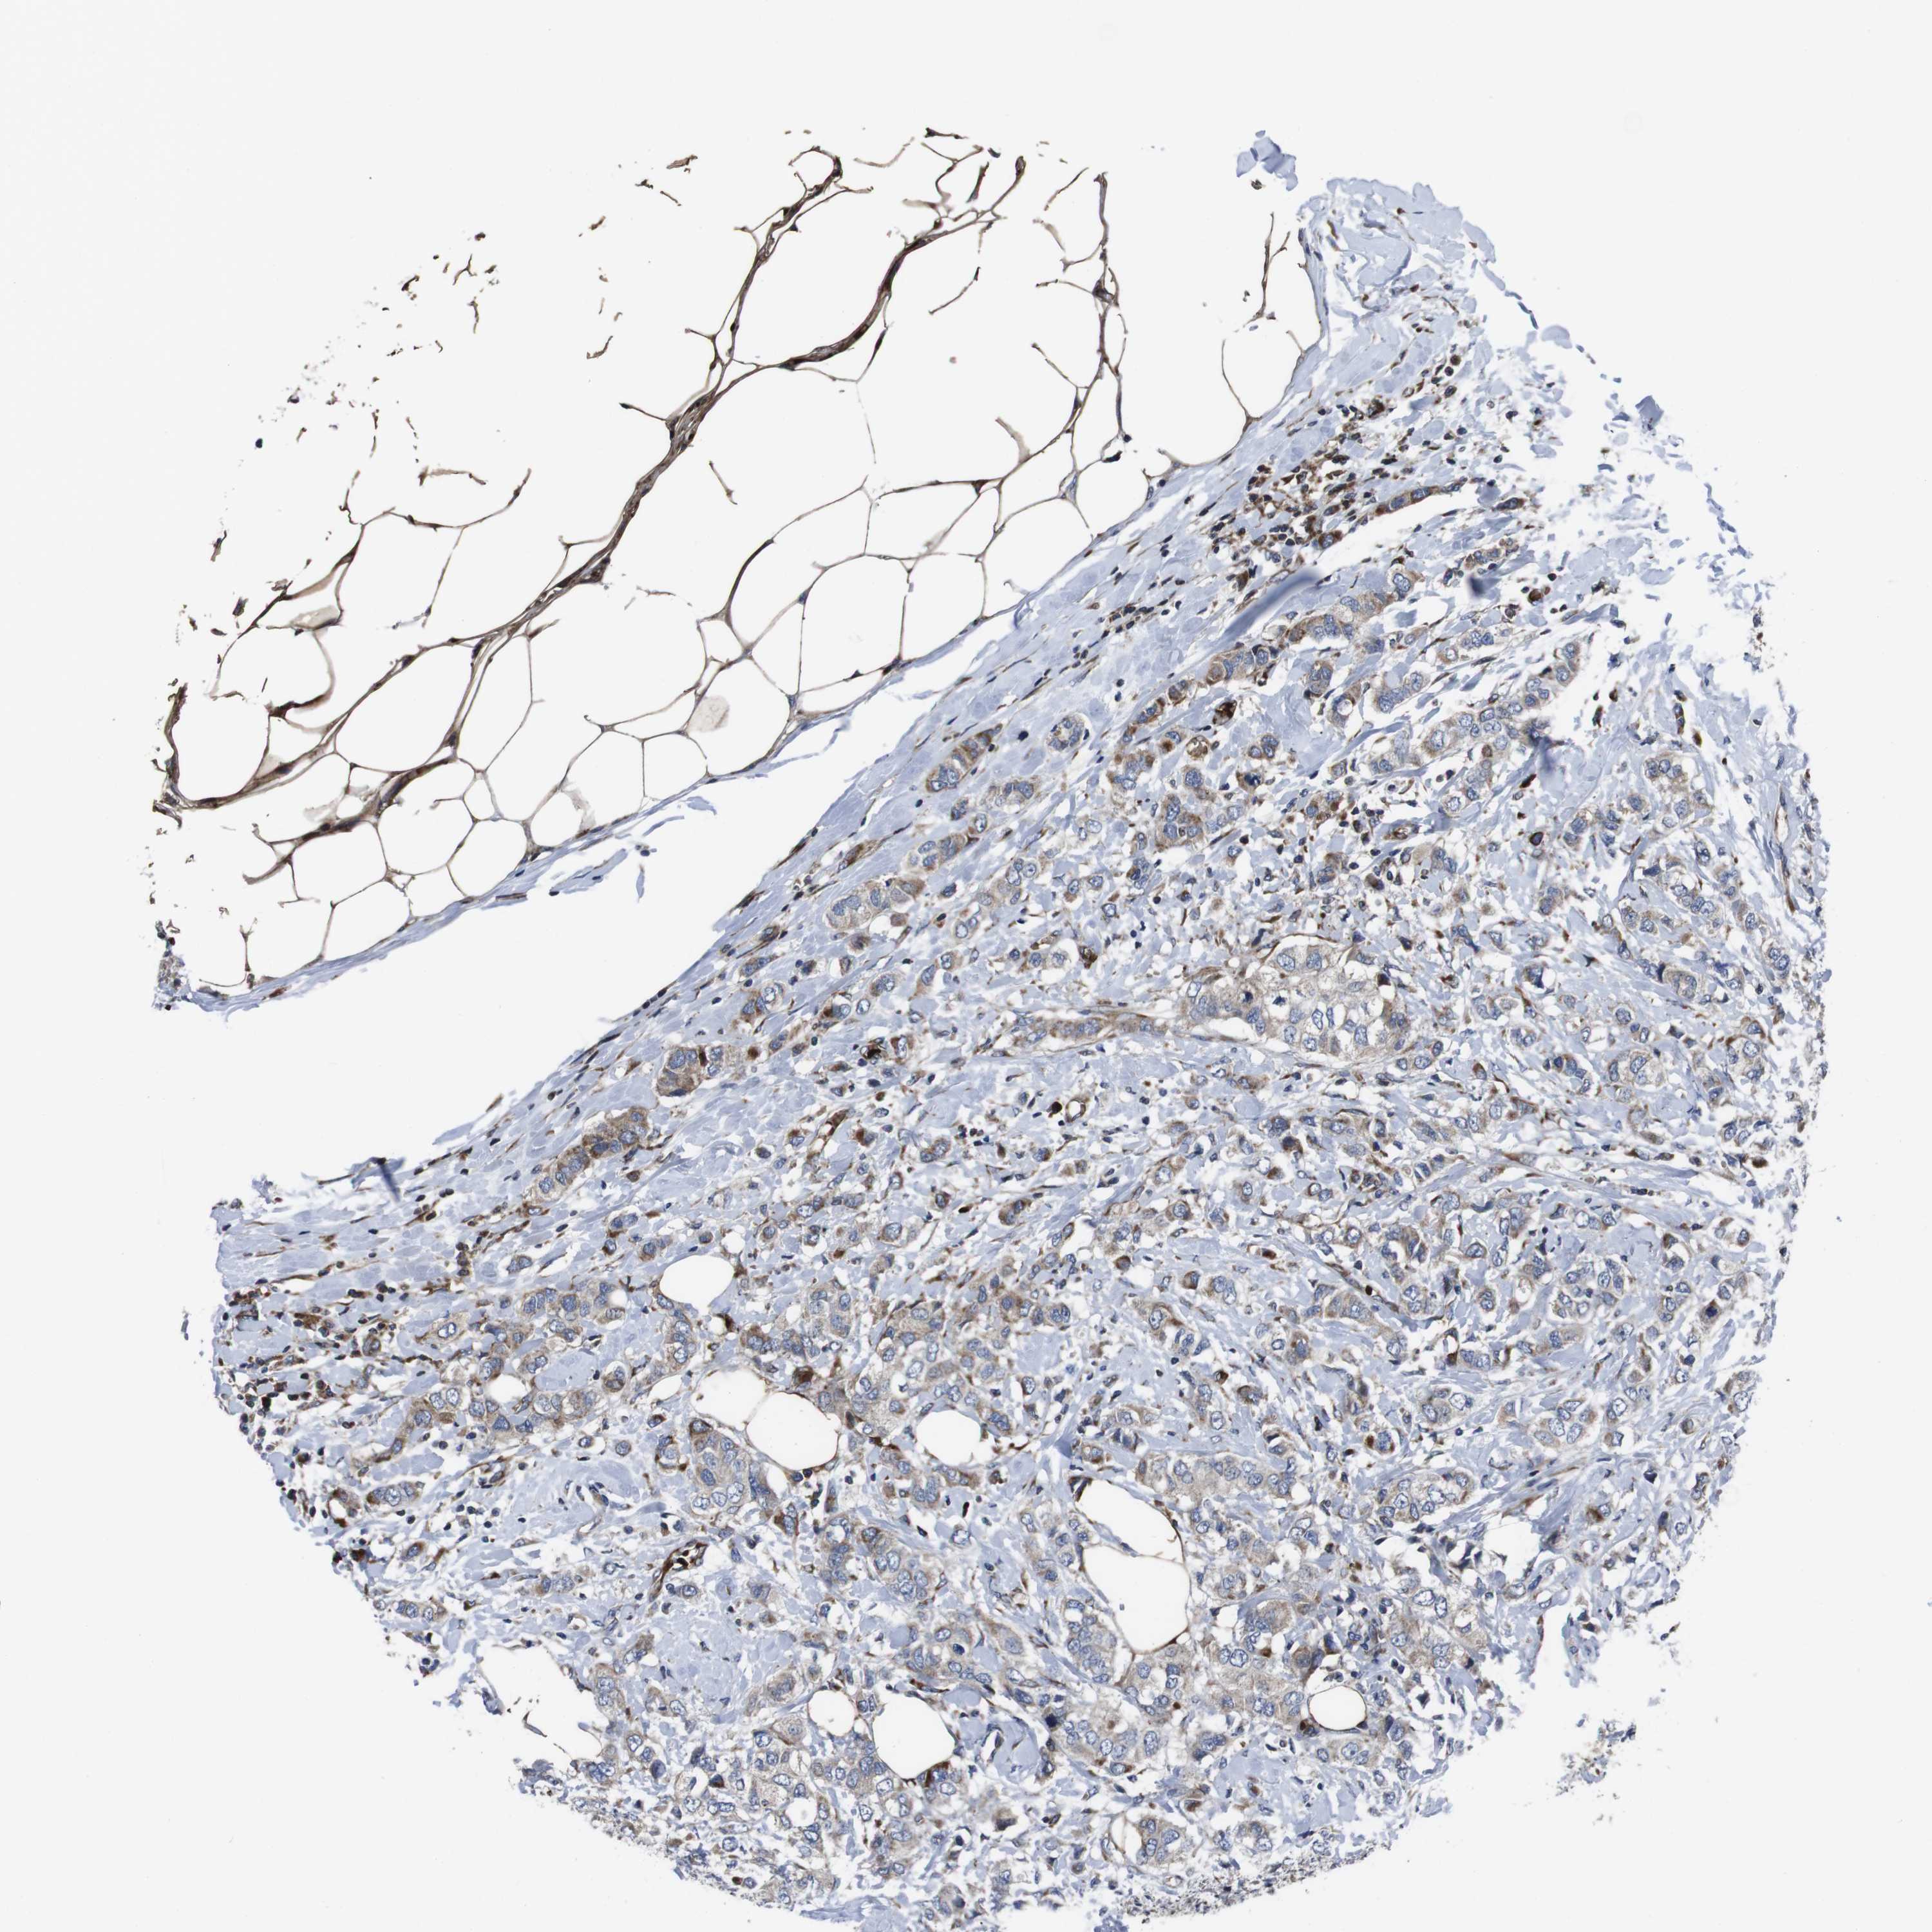

BRCA TCGA BRCA VALIDATION PROTEIN EXPRESSION

ANTIBODIES

AND

VALIDATION